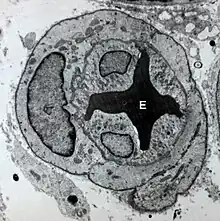

Micrographie électronique à transmission montrant la vasoconstriction d'un microvaisseau par les péricytes et les cellules endothéliales entraînant la déformation d'un érythrocyte (E).